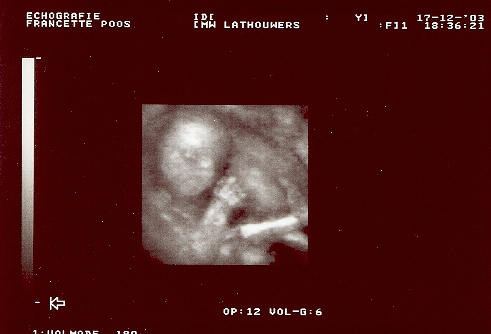

Vandaag gaan we terug naar Francette Poos voor een “pretecho”. Wij zijn erg benieuwd hoe het met je gaat, of je al goed gegroeid bent. Ook wordt er een 3D echo gemaakt. Hopen dat het lukt. Hier moet je namelijk wel goed voor stil liggen. Over het algemeen ben jij een rustige baby.

De echo is erg leuk geweest, ook de 3D echo is goed gelukt. Nog 7 weken en dan zullen we zien hoe jij eruit ziet. Mama wordt namelijk met 38 weken ingeleid, omdat men zeker plaats moet hebben op de intensive care voor jou.